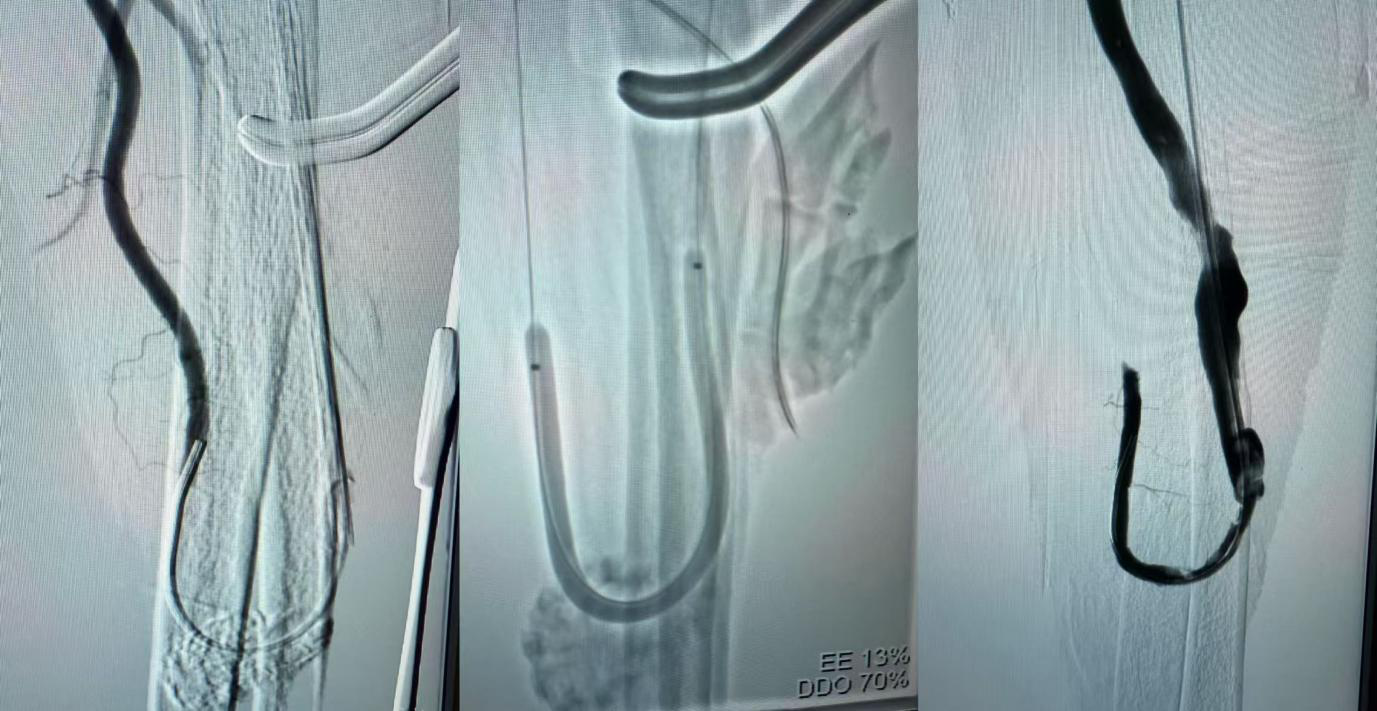

手术过程中采用局部麻醉,先在患者前臂内瘘血管的合适部位做一小切口,精准找到血栓位置后,小心将堵塞血管的血栓完整取出;随后,透视下将导丝和导管通过狭窄的吻合口,造影确认为动静脉吻合口处闭塞,采用球囊扩张技术,对动静脉吻合口处的狭窄段进行了扩张,恢复血管的正常管腔直径,确保血流能够顺畅通过。整个手术过程紧凑而有序,历时约1小时顺利完成。术后即时造影显示内瘘血管血流恢复通畅,前臂内瘘处可以触摸到清晰、有力的血管震颤——这意味着老人的透析“生命线”成功重启!当天晚上,王先生就顺利进行了血液透析治疗,体内的代谢废物和多余水分得到有效清除,不适症状也明显缓解。

▲扩张内瘘吻合口,解除了血管狭窄闭塞